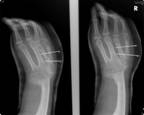

Follow Up

Xrays